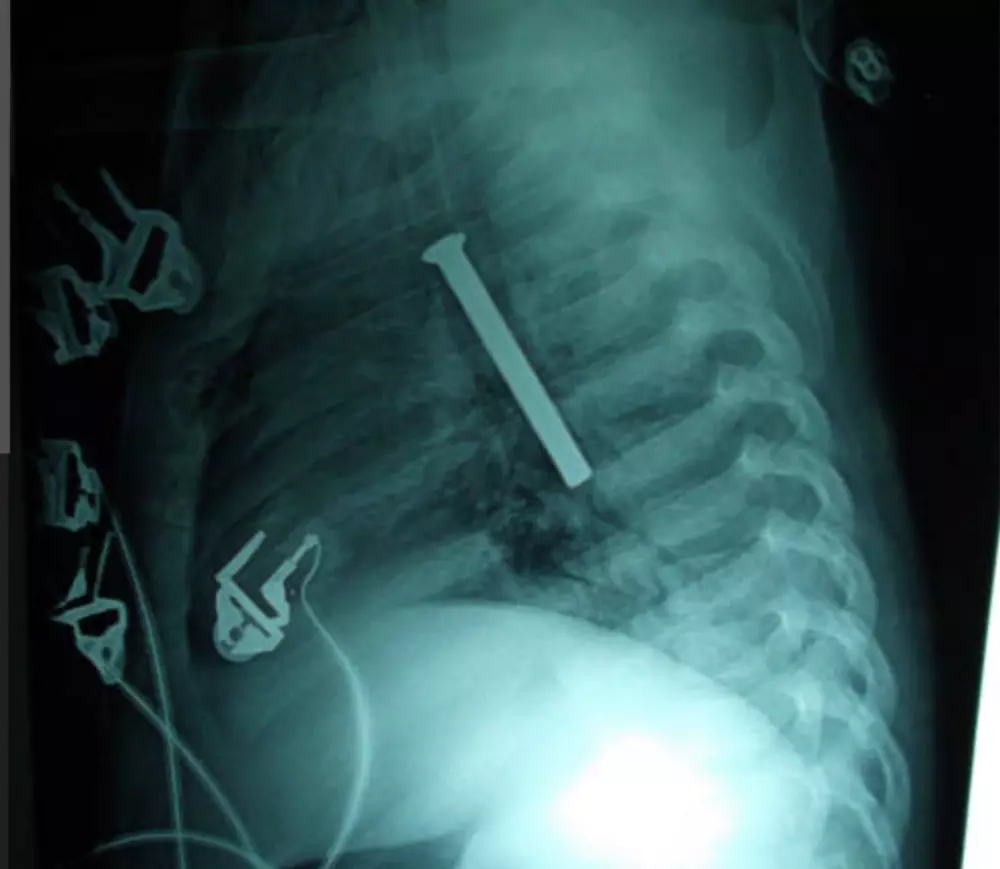

قراءة تقارير التحاليل والأشعه وتقديم ملخص ووصف استشاري عام دون تشخيص أو وصفه علاجيه وتوجيهك لزيارة الطبيب المختص ثمن قراءة تقرير التحليل 10 دولار لكل تقريرين والأشعه كذلك وإن كان هناك استشارات أو أسئله فسيكون ثمن ال5 أسئله 10 دولار ونؤكد على أن المعلومات المقدمه لا تغني عن زيارة الطبيب ولا تعتبر تشخيص نهائي ولا أصف لك دواء فقط اطمئنك على حالتك عوفيتم